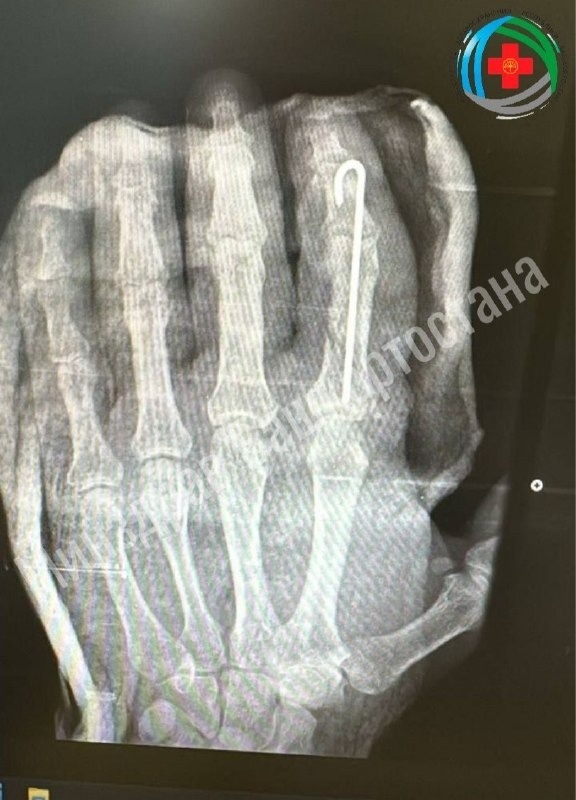

Жителю Башкирии пришили отрубленный топором палец